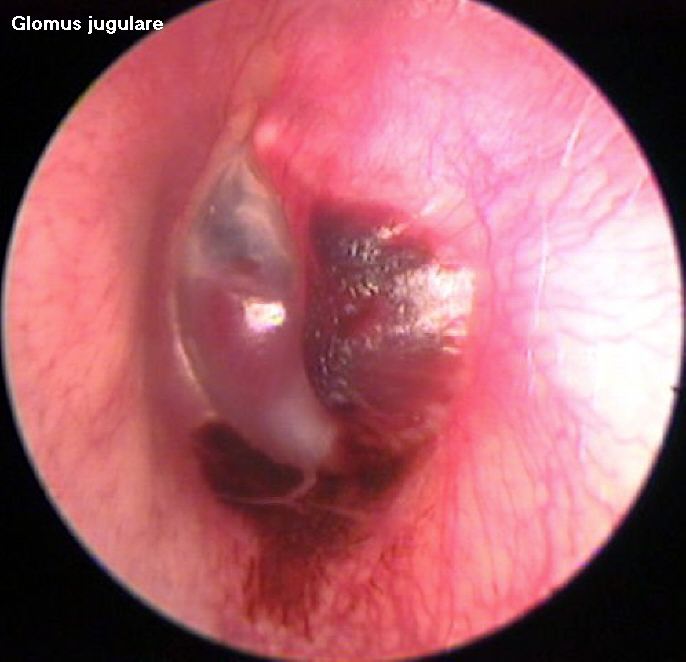

Otoendoscopic picture of Glomus jugulare

Clinical features: Otoscopic examination reveals a characteristic, pulsatile, reddish-blue tumor behind the tympanic membrane that often is the beginning of more extensive findings (ie, the tip of the iceberg). When the drum is examined under a microscope will show a pulsation of the reddish mass behind the drum. On seigalisation the mass blanches. This sign is known as Brown's sign. This is pathognomonic of glomus tumor.